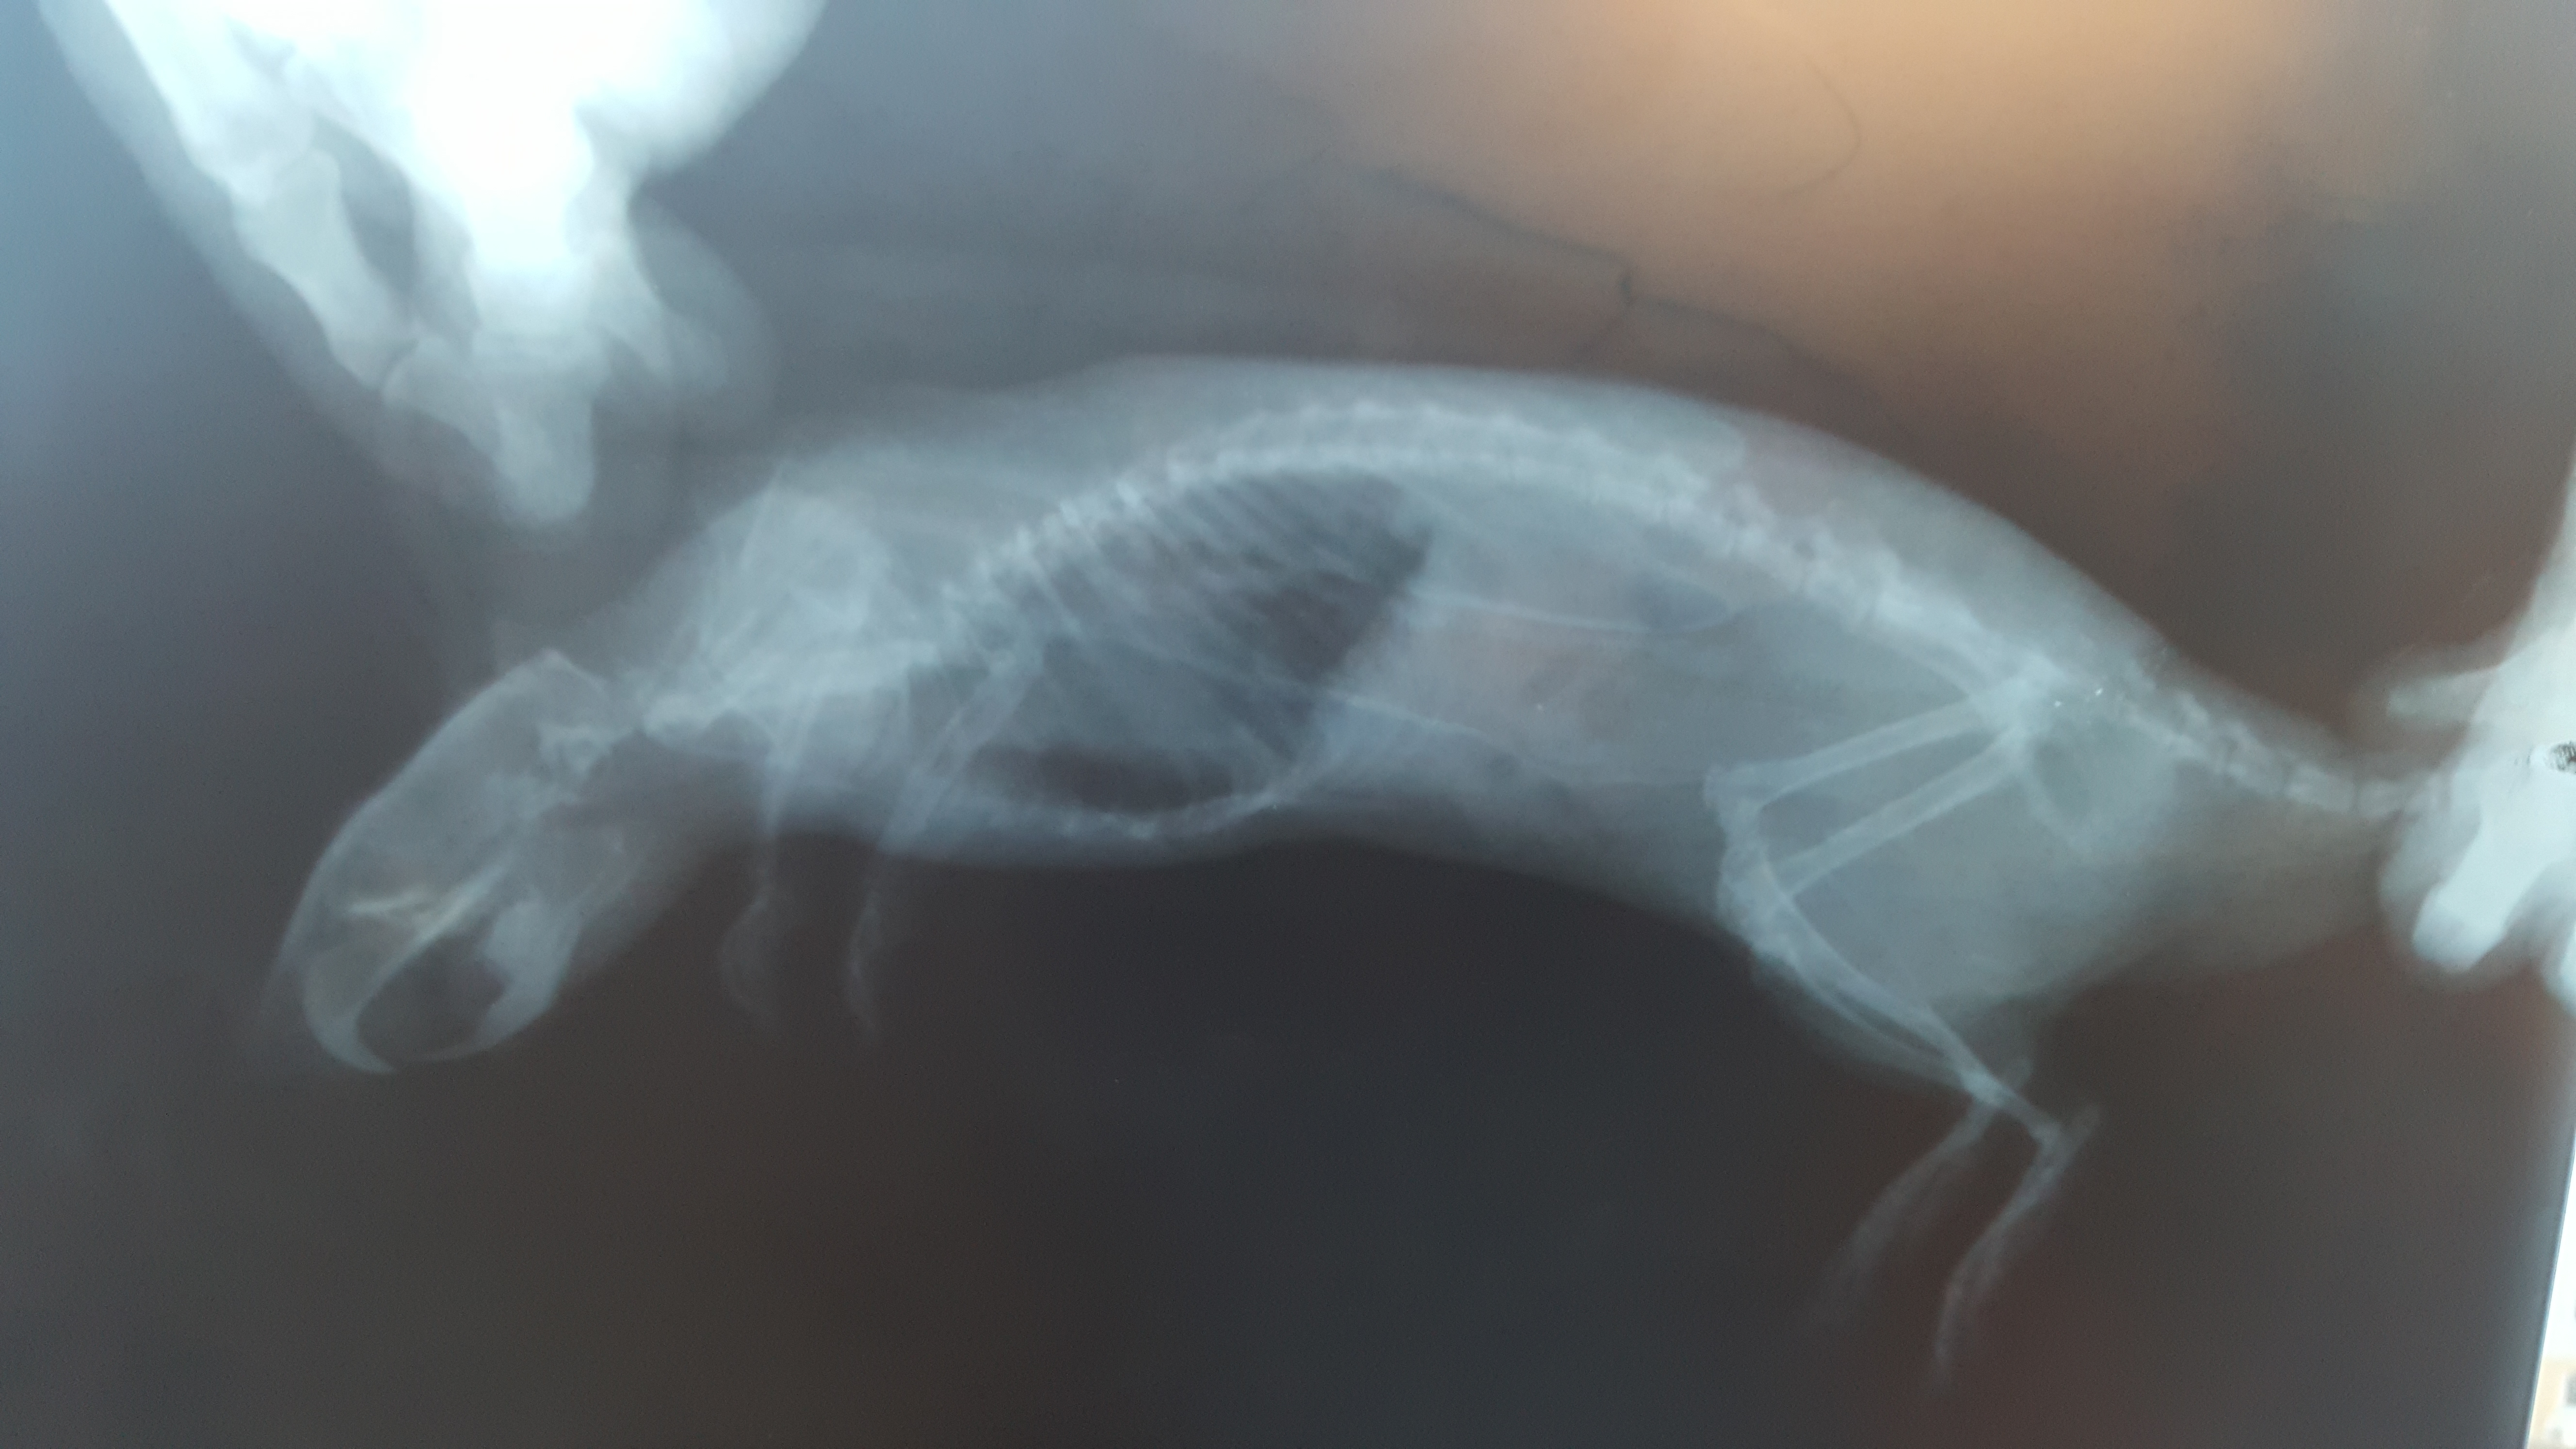

13 дней назад (11.04.18) вернулись из отпуска (оставляли крысика бабушке) и застали такую картину. Тяжелое дыхание грудной клеткой, кашляет порфирином из рта, вялость, ухудшение аппетита, активность 30%. Поехали к ветеринару, диагноз - отек легких (застойная пневмония), подозрение на перикардит и онкопроцесс.